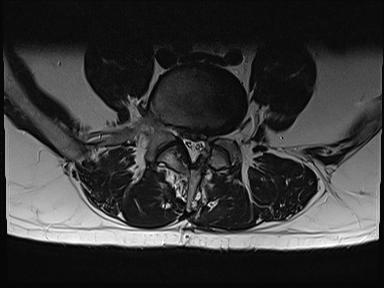

Ich werde mal 2 Bilder der MRT Untersuchung hochladen.

Heutiges MRT ergab das die Bandscheibe immer noch soweit raus ist wie vor 2 Monaten. Also ist nicht weiter gerutscht. Das Narbengewebe ist nur noch schwach auf Kontrasmittel ansprechbar was bedeutet das der Heilungsprozess noch nicht abgeschlossen ist. Einen richtigen berricht bekomme ich erst am montag leider.

Die Ncs können sich nicht ganz erklären wieso es so ist bei mir aber dad die bamdscheibe schon ganzschön raus ist aber noch genug liquorwasser da ist das die cauda Fasern frei schwimmen.

Narbengewebe ist da und umschließt den dura Sack was dazu führt das de4 nerven Strang nicht ausweichen kann....